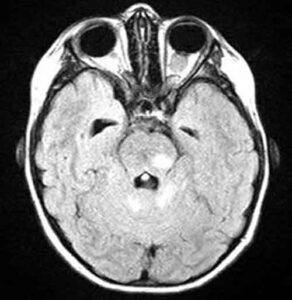

neurofibromatosi